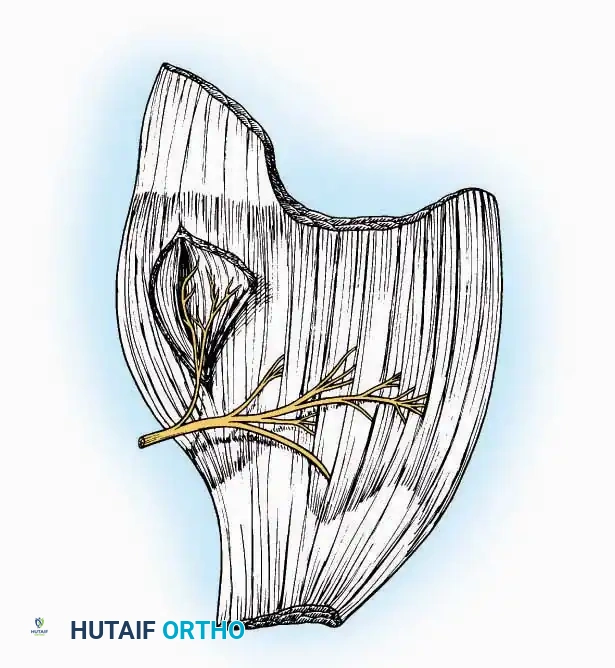

Approaches to the Interphalangeal (IP) Joints

Indications: Arthrodesis for hammer toe deformities, excision of intra-articular osteophytes, or reduction of irreducible dislocations.

Surgical Technique:

* Great Toe: Make a 2.5 cm longitudinal incision strictly on the medial midaxial aspect of the toe.

* Fifth Toe: Utilize a lateral midaxial incision to avoid interdigital maceration.

* Lesser Toes (2nd, 3rd, 4th): Approach the IP joints through a dorsal longitudinal incision placed just lateral to the corresponding extensor digitorum longus (EDL) tendon.

* Deep Dissection: Carry the dissection sharply through the subcutaneous tissue and superficial fascia directly to the joint capsule.

* Neurovascular Protection: Reflect the skin edges with meticulous care. Retract the dorsal digital nerves and vessels dorsally, and the plantar nerves and vessels plantarward.

* Capsulotomy: Open the capsule either transversely (for joint resection/arthrodesis) or longitudinally (for exploration), exposing the articular surfaces.